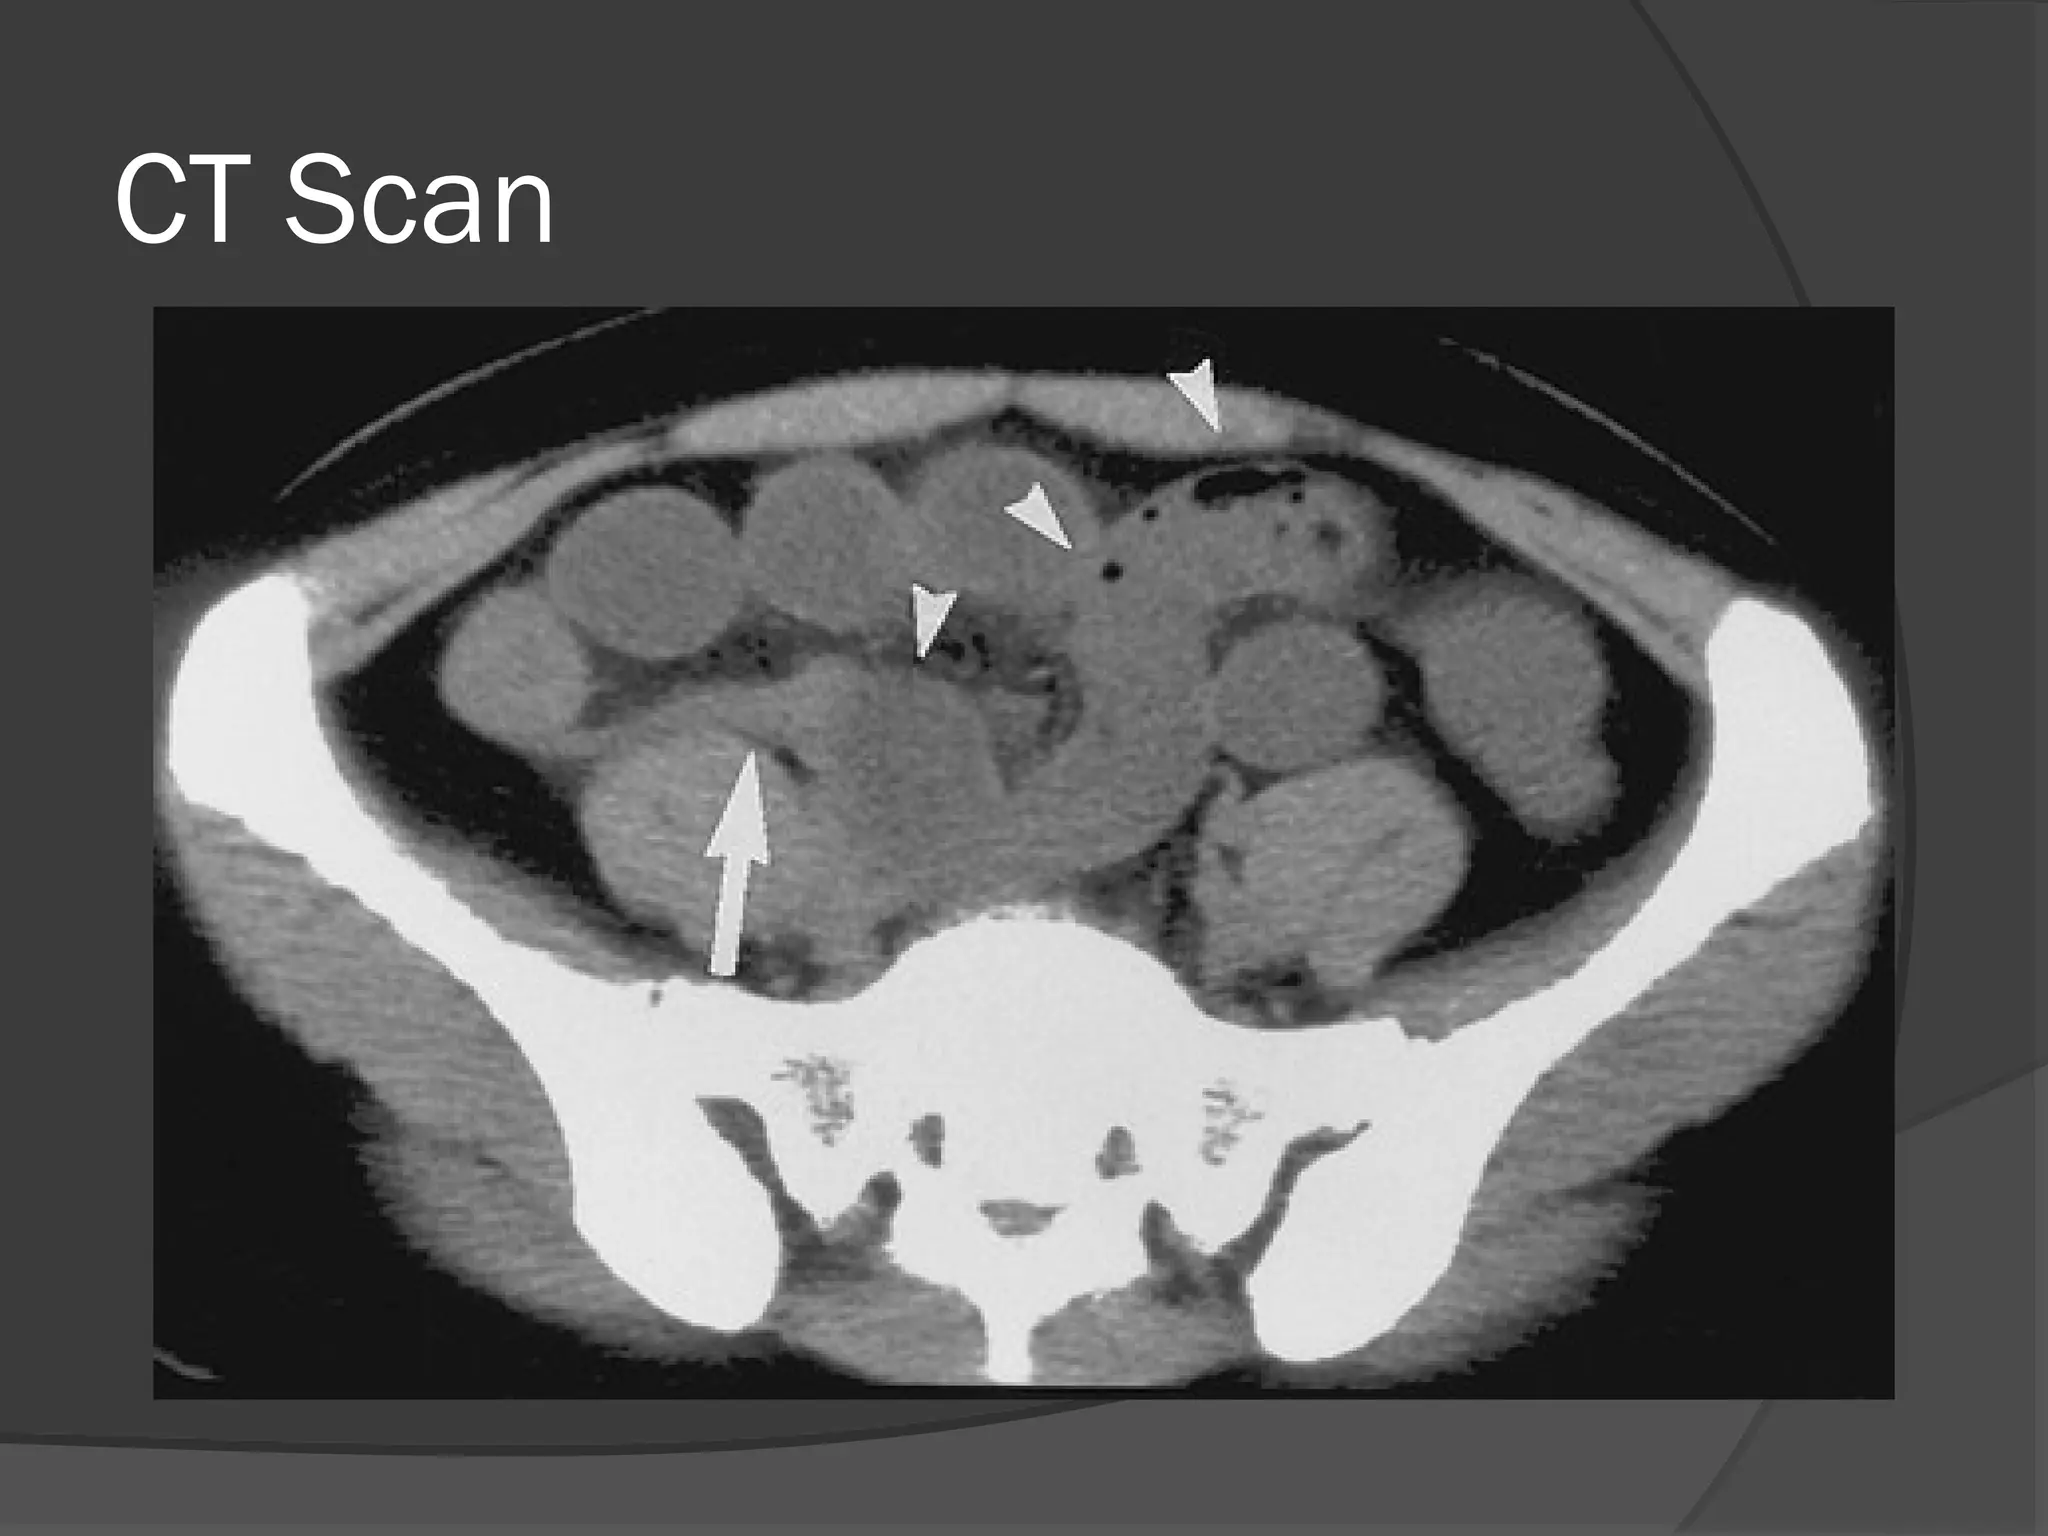

CT

 Useful to detect…

• Lesions

• Colonic Tumors

• Hernias

• Bolus

CT Scan

CT  Useful todetect… • Lesions • Colonic Tumors • Hernias • Bolus